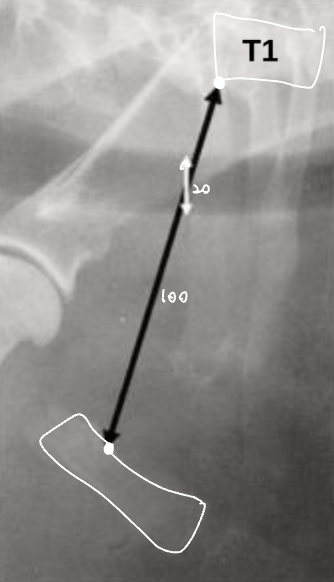

Tracheal diameter 재는 법법

• Thoracic inlet과의 비율로 나타낸다.

- T1의 끝부분에서, 1번 sternum의 가장 오목한 부분 (Thoracic inlet)을 선으로 잇고 길이를 잰다.

- Trachea의 길이를 잰다.

- 비율은 보통 0.2 정도.

(단두종에서는 정상적으로 더 작다.)